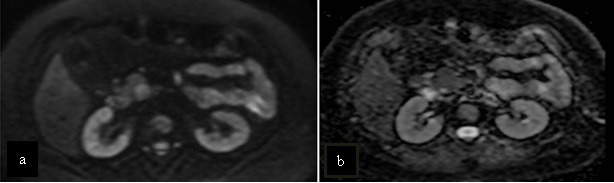

Paciente femenina de 48 años de edad que ingresa a Hospital Sanatorio Franchin por síntomas de cefalea y mareos, cuadro que se hace progresivo, presentando síncopes y posteriormente alteración del estado de conciencia. Los exámenes clínicos revelan una glucosa de 40 mg/dl, concomitante con insulina alta y péptido C elevado. Ingresa de forma programada para realización de duodeno pancreatectomía el 29 de mayo de 2021. Imágenes diagnósticas muestran estudio trifásico de tomografía de abdomen, lesión nodular en la cabeza del páncreas con ávido realce en fase arterial que en resonancia magnética se observa hiperintensa en T2, presenta restricción con la difusión y caída de la señal en el ADC. Además presenta realce tras la administración de contraste con gadolinio.

La resonancia magnética es el otro estudio de imagen no invasivo que nos permite la detección de la lesión con una sensibilidad mayor que la de la tomografía, del 85% al 95%, donde los insulinomas presentan un realce tras la administración de contraste con gadolinio y secuencias T1 sin contraste son lesiones hipointensas y en secuencias T2 son hiperintensas.

La resonancia magnética confirmó aún más el diagnóstico de las lesiones ya previamente visualizadas en tomografía en esta revisión, con realce de las lesiones en secuencias T1 y contraste con gadolinio, y en las secuencias funcionales con restricción de la lesión y caída de la señal en el mapa de ADC.